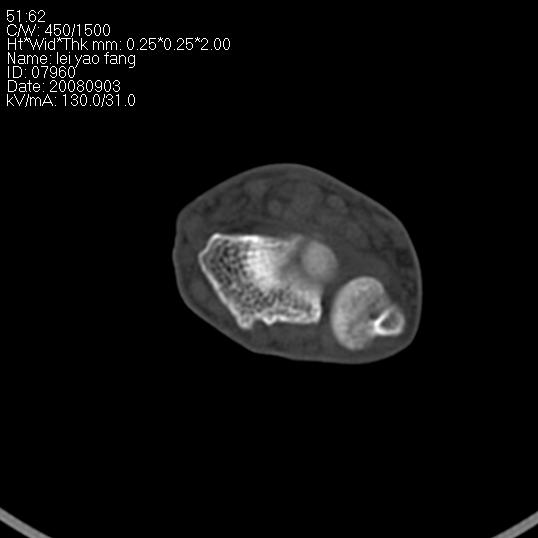

以下是引用杀毒软件在2008-9-4 17:41:00的发言:[br]考虑----舟骨囊肿